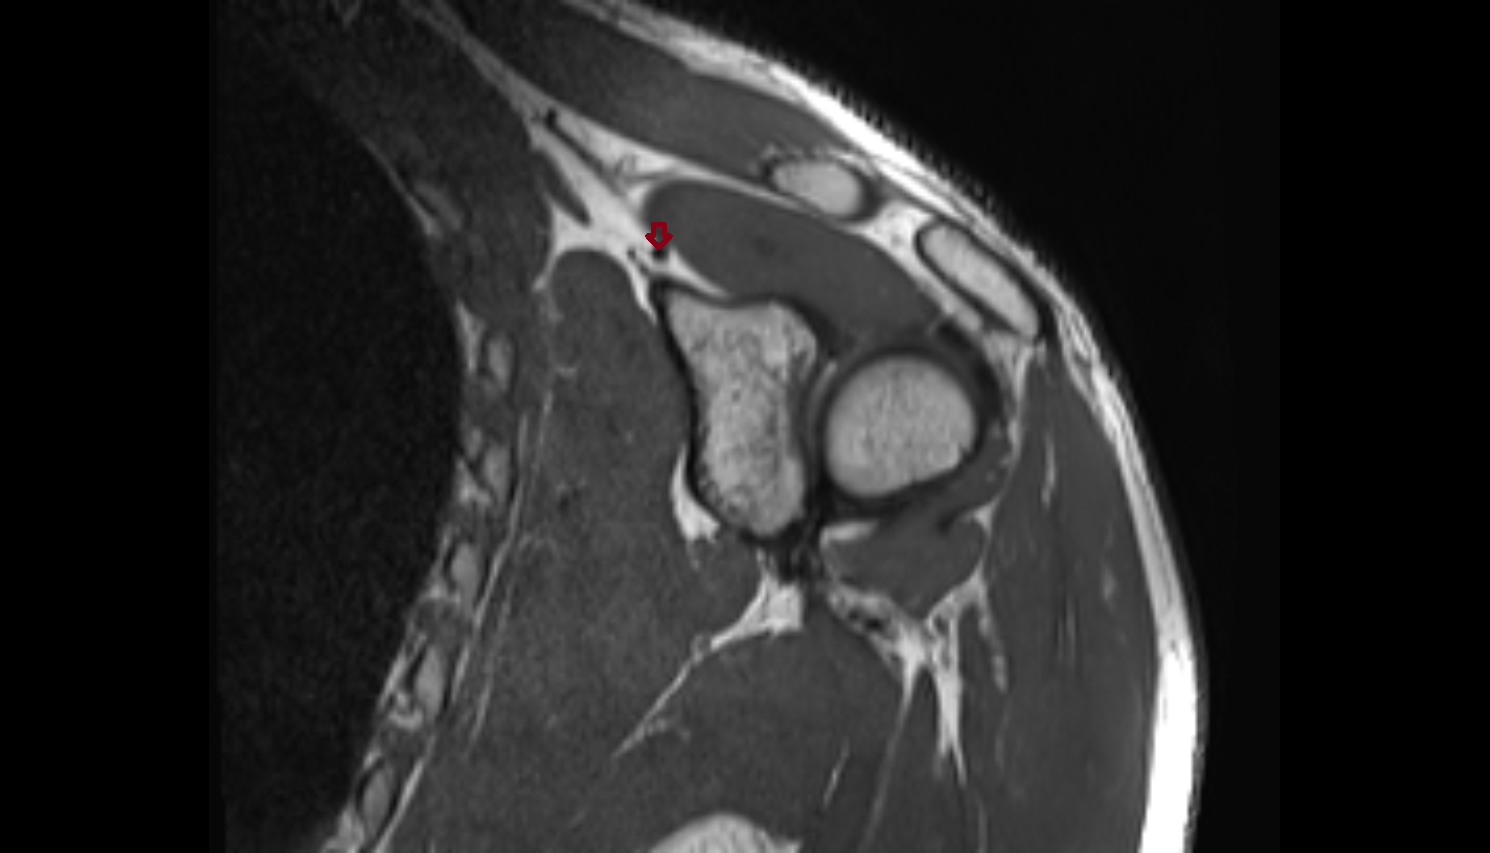

- Temporomandibular joint

- Articular disc of temporomandibular joint

- Articular eminence

- Mandibular condyle

- Mandibular fossa